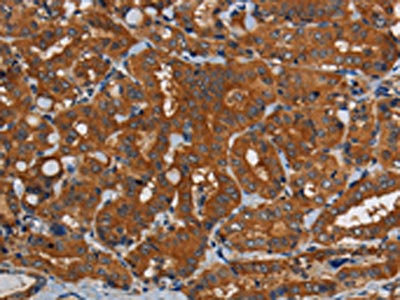

The image on the left is immunohistochemistry of paraffin-embedded Human thyroid cancer tissue using CSB-PA126186(PDE5A Antibody) at dilution 1/50, on the right is treated with synthetic peptide. (Original magnification: ×200)